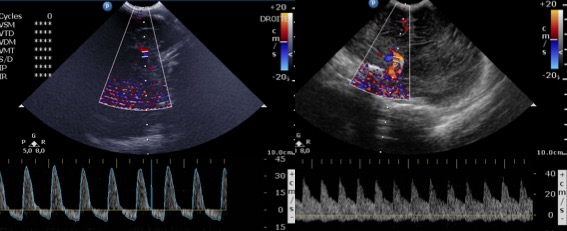

- l’échographie, couplée au Doppler est l’examen de référence, non invasif, fait au lit du patient et répétable, il permet de diagnostiquer des lésions cérébrales associées et de suivre l’évolution de la taille ventriculaire et du retentissement hémodynamique

- le Doppler permet de calculer l’index de résistance = (systolique-diastolique)/moyenne qui est un bon reflet de l’hémodynamique intracrânienne

-

Echo-Doppler montrant une HTIC sévère avec reverse-flow (à gauche), et correction hémodynamique après ponction soustractrice (à droite) - l’IRM est importante à visée pronostique